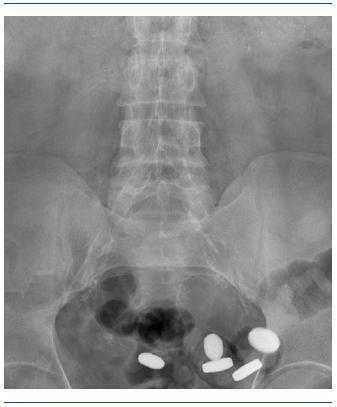

Varón de 59 años, incluido en programa de hemodiálisis desde 2004 por nefropatía diabética. Desarrolla hiperparatiroidismo secundario grave (PTHi 1.124 pg/ml) debido en parte a mala adherencia a dieta y varios tratamientos: carbonato cálcico, sevelamer y cinacalcet. Finalmente, y ante la persistencia de hiperfosforemia, inicia tratamiento con carbonato de lantano (Fosrenol®) a dosis de 2.000 mg/día. Unas semanas más tarde refiere molestias abdominales. En la Rx simple de abdomen se aprecian al menos ocho comprimidos de este medicamento alojados en la luz intestinal. A pesar de nuestras advertencias, el paciente no había masticado los comprimidos antes de su deglución, como es preceptivo para su eficacia.

Figura 1. Comprimidos de carbonato de lantano.